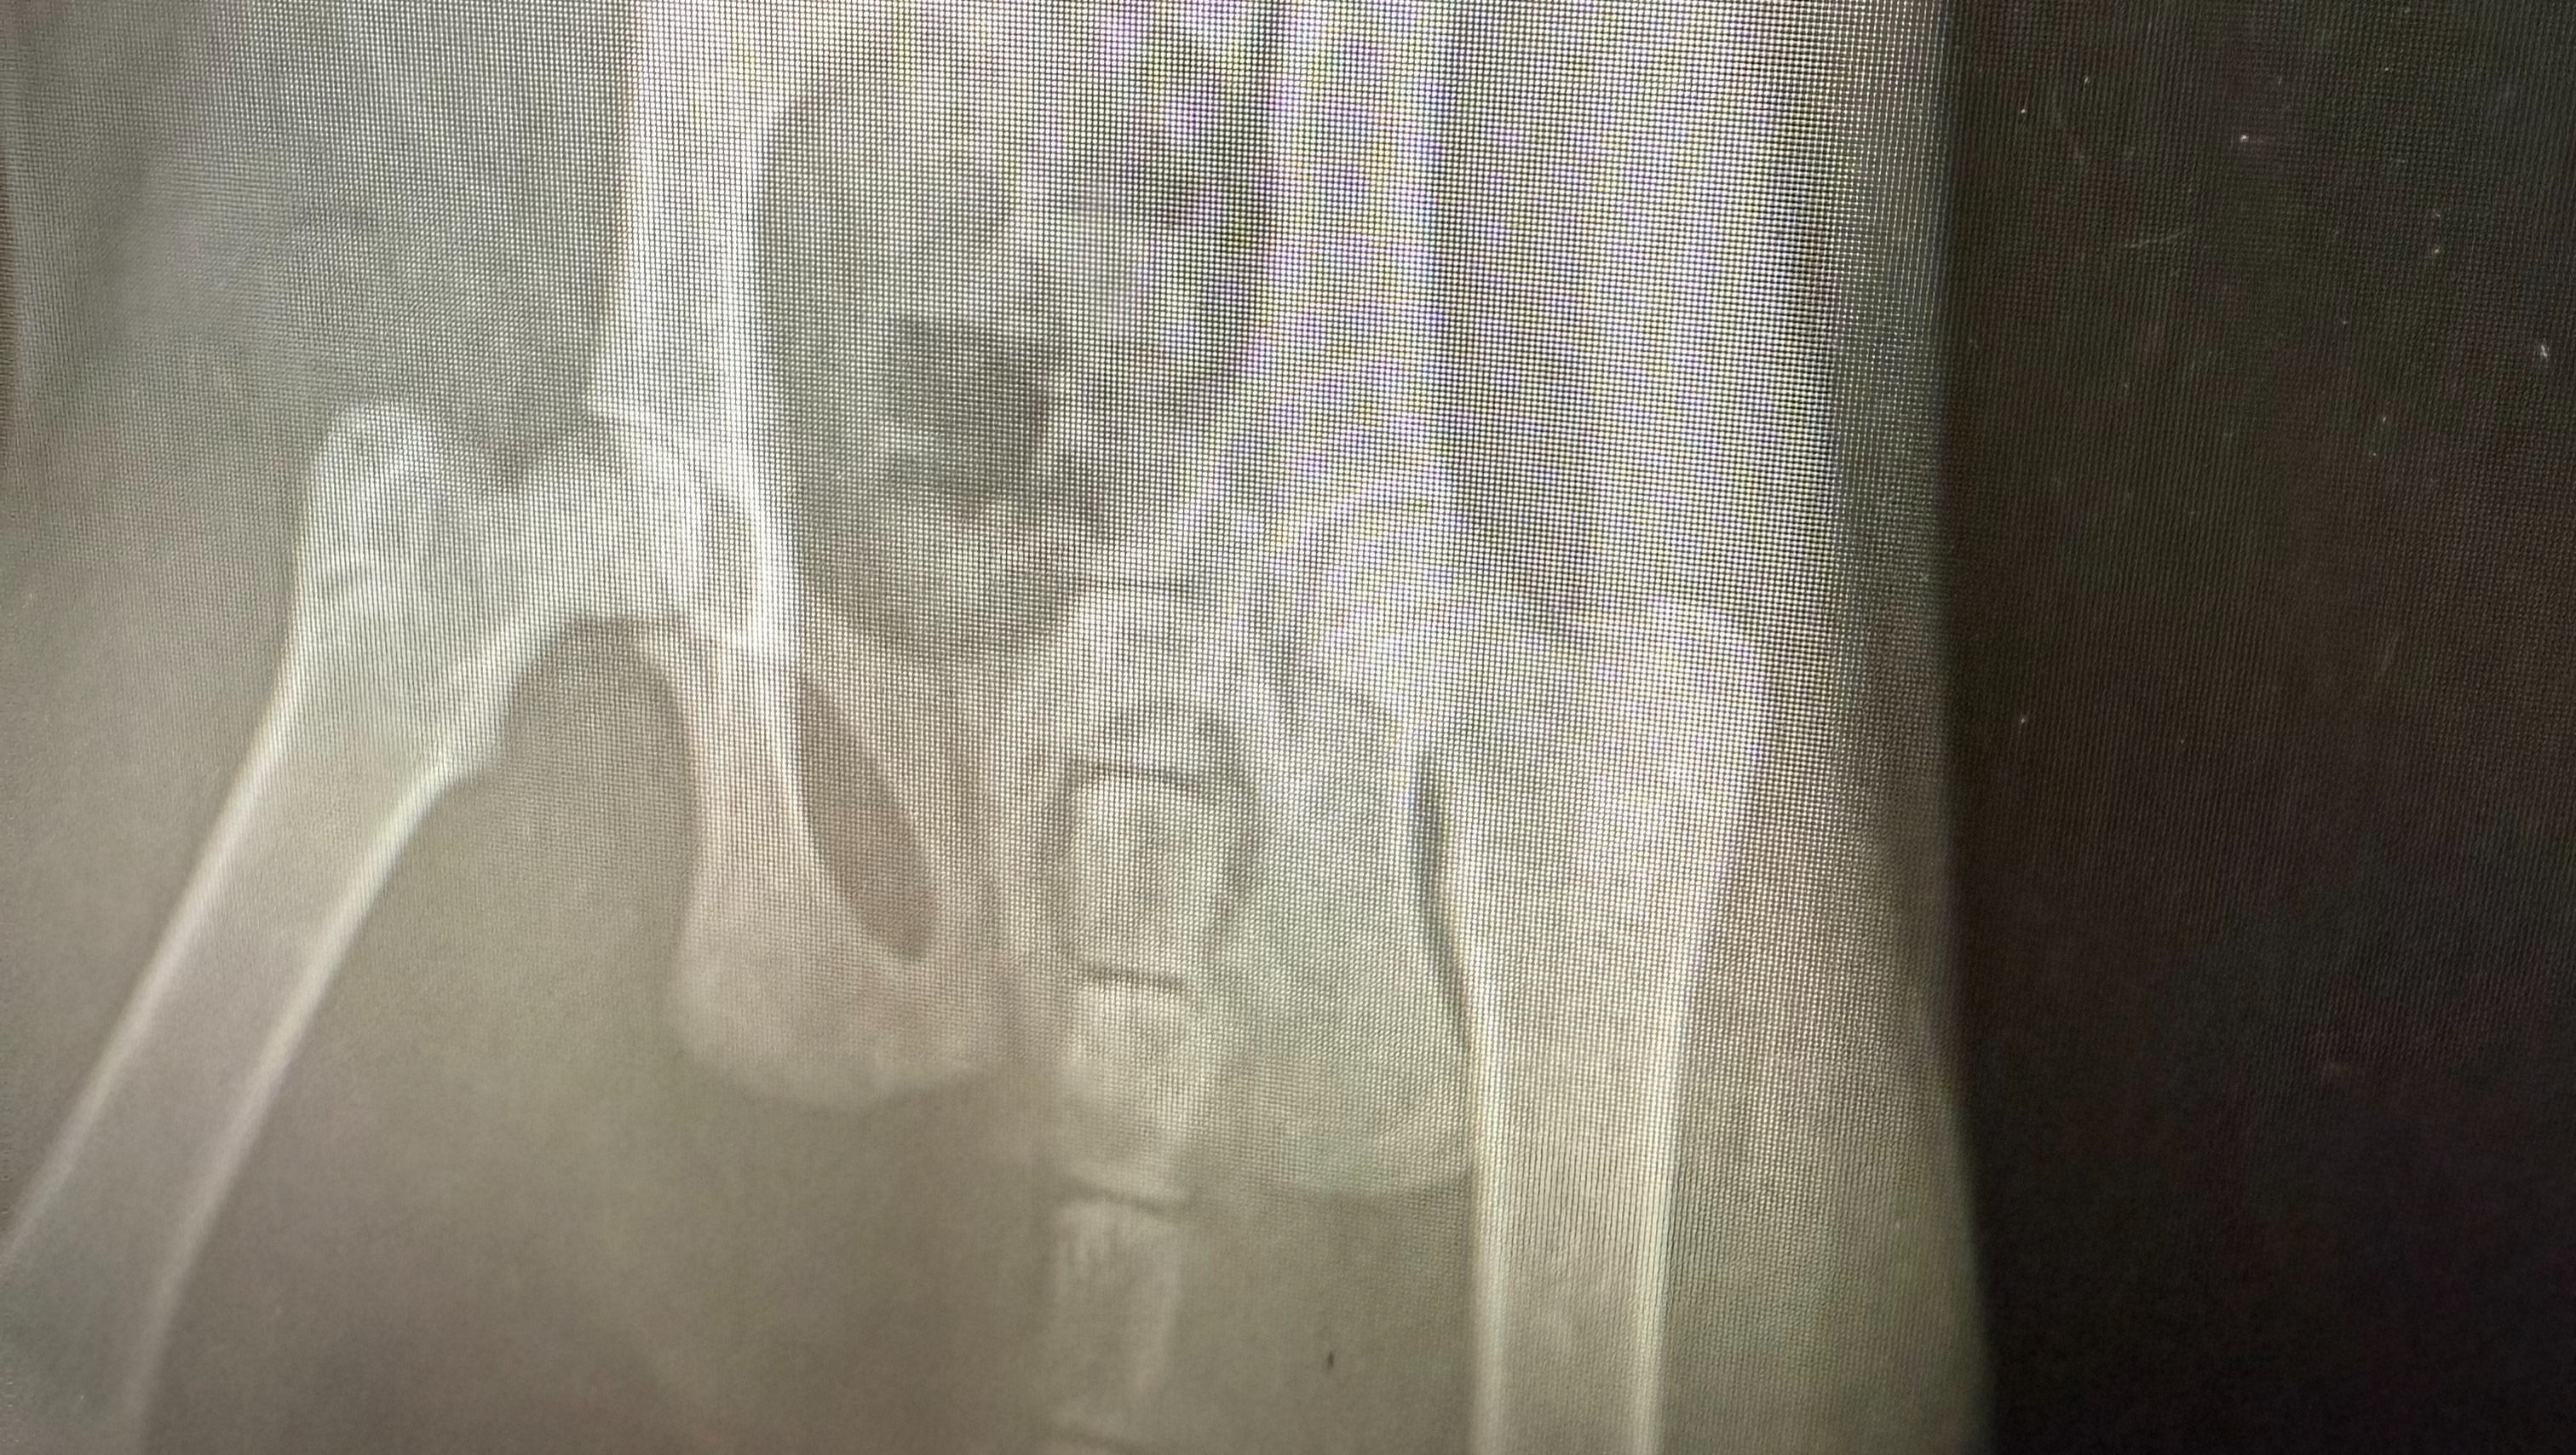

The cat has a confirmed concussion, a fractured pelvis, and internal organ damage. Treatment is expected to cost at least $7,000, and we are working to raise the funds for the medical care needed. Volunteers from PurrificHome and Flushing Cat Shelter are helping with the situation, but we urgently need your support.